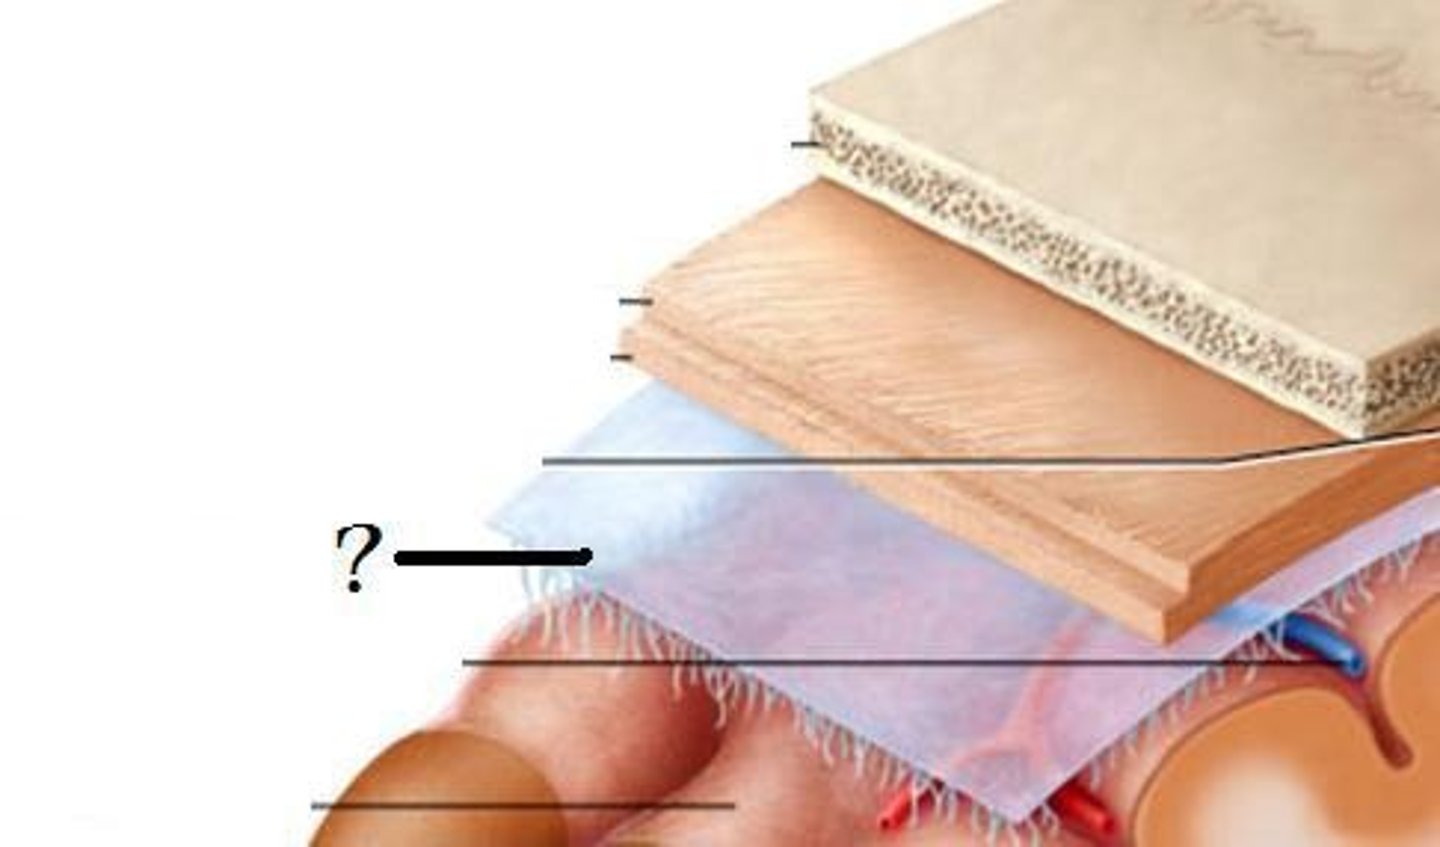

3 layers make up the meninges

dura mater, arachnoid mater, pia mater

dura mater

outer periosteal layer & inner meninges layer

arachnoid

middle layer of meninges; weblike appearance that attaches it to deepest layer

arachnoid trabeculae

subdural space

space between dura mater and arachnoid mater

subarachnoid space

skin of scalp

arachnoid mater

pia mater

the delicate innermost membrane enveloping the brain and spinal cord.

leptomeninges

The pia mater and arachnoid together